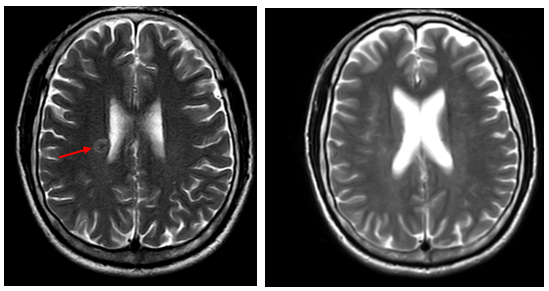

- MRI sọ não:

Hình 4. Trên phim chụp MRI sọ não: Rải rác trong nhu mô trên và dưới lều có các nốt ngấm thuốc, lớn nhất vị trí cạnh não thất bên bên phải đường kính ~11mm – Theo dõi tổn thương thứ phát

Cộng hưởng từ sọ não:

Trước điều trị Sau 3 tháng điều trị

- Sau 6 tháng điều trị: Nhu mô não vùng trên và dưới lều tiểu não: hình dạng và cấu trúc bình thường, tín hiệu đồng nhất, ranh giới chất trắng và chất xám rõ. Không thấy tổn thương khu trú hoặc lan tỏa.